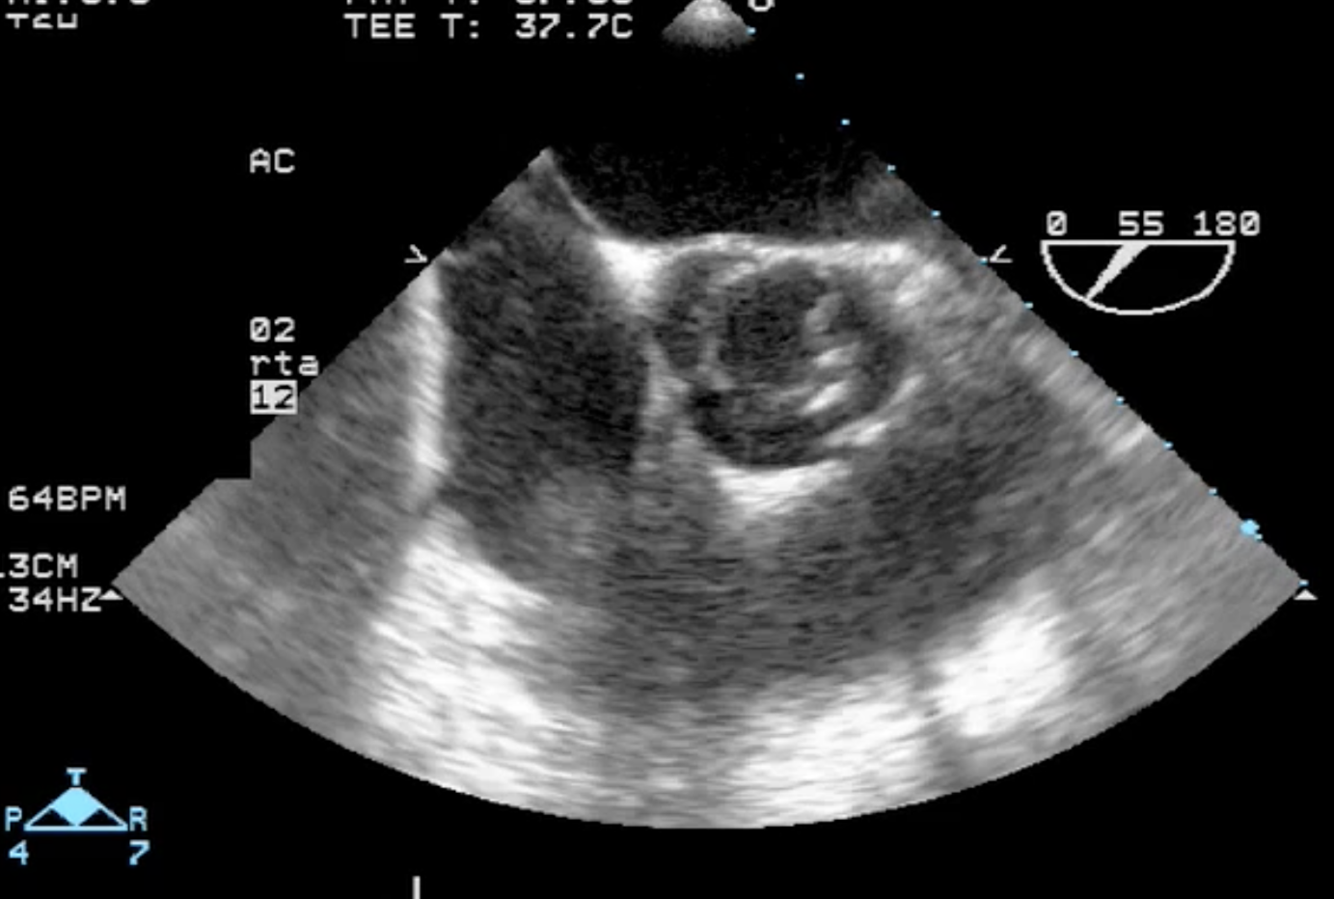

Bicuspid aortic valve (fused right and left coronary cusps)

What is the anatomical valve abnormality of Congenital bicuspid aortic valves (in order)?